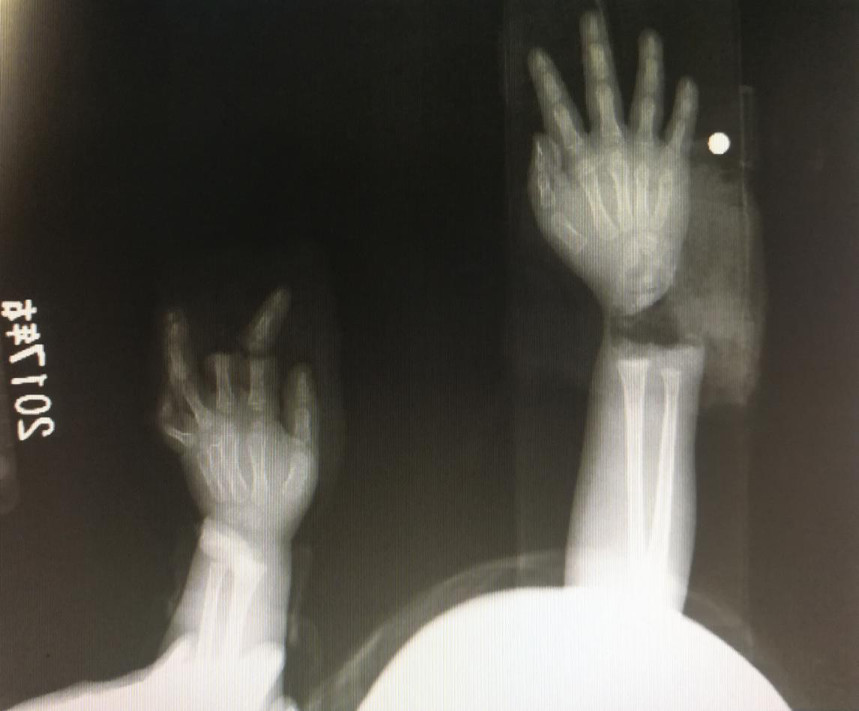

“急診在哪,急診在哪”,伴隨著一聲聲急促的問詢,一位年輕女士抱著渾身是血的小孩疾步前往急診室,懷里的小孩在疲憊與疼痛的交織下,時(shí)睡時(shí)醒。鑒于小孩的情況,急診醫(yī)生迅速安排給小孩拍了X光片,影像片結(jié)果顯示小孩左手手腕完全離斷,右手中、食指離斷,距離事發(fā)時(shí)間已經(jīng)3個(gè)多小時(shí),需盡快安排手術(shù)。

經(jīng)過長(zhǎng)達(dá)5個(gè)多小時(shí)的手術(shù),小宇(化名)終于被送出了手術(shù)室,離斷的手腕和手指均已完成再植,但關(guān)于斷指的存活與否還需要經(jīng)過一個(gè)十天的觀察期。小宇的主治醫(yī)生是長(zhǎng)沙年輪骨科醫(yī)院手足外科馬思成醫(yī)生,據(jù)馬醫(yī)生介紹,小宇受傷情況比較嚴(yán)重,失血過多,而且兩個(gè)手都存在完全離斷的情況,手術(shù)時(shí)安排了兩組醫(yī)生同時(shí)進(jìn)行,整個(gè)手術(shù)過程比較順利,目前小宇還處于觀察期。